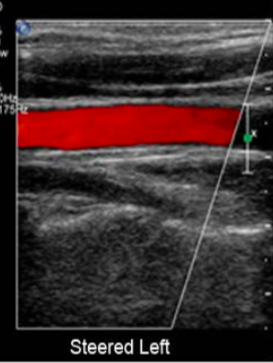

In which direction is this image steered?

to the left

steering color doppler imaging to left → diagonal border points to 6-9 o’clock region